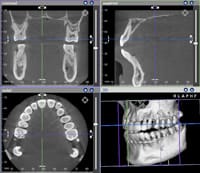

顎関節の正確な観察や矯正歯科以外の治療にも役立つ

さらに、当院では、機能的な咬み合わせを確立するために、顎関節の調和を優先させた治療をこころがけています。そのため、顎関節部のCT撮影は実際に目で見えない顎関節の状態を知る上で非常に有用な手段となっています。

また、矯正歯科治療のためだけでなく、顎関節症の患者さんや重度の歯周病の患者さんなどに対しても、他院からの依頼を受けてCT検査を行っています。